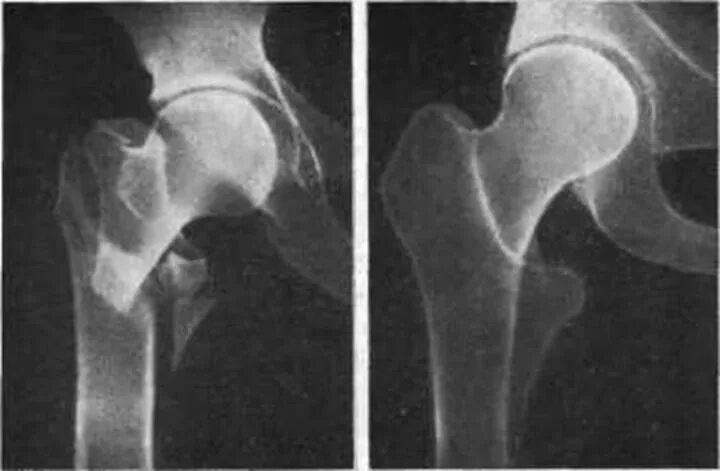

Перелом 1 3 бедра